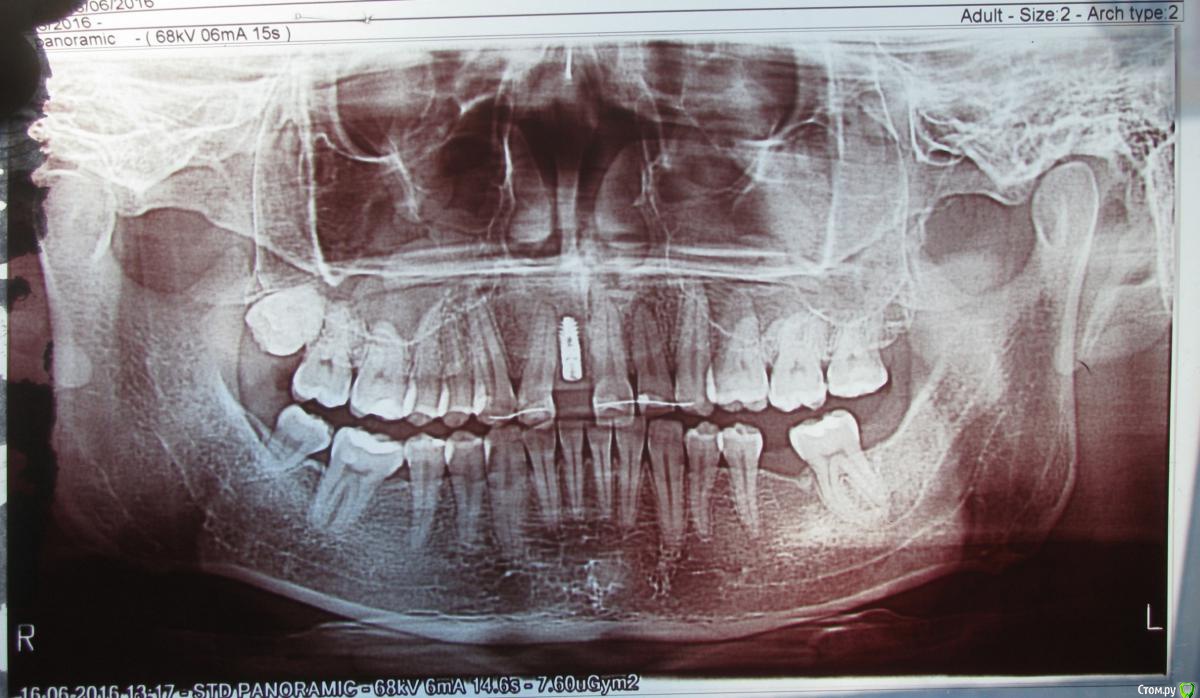

Scander Опубликовано 20 января, 2017 Поделиться Опубликовано 20 января, 2017 Смотрю на снимок и возникает ощущение, что имплант почти касается корня соседнего зуба.Насколько опасно такое близкое соседство? Ссылка на комментарий

колесников Опубликовано 20 января, 2017 Поделиться Опубликовано 20 января, 2017 Здравствуйте! Корни передних зубов обычно имеют наклон в сторону губы,имплант же ставится в нёбном положении. Они не пересекаются и не соприкасаются,это можно увидеть на трёхмерном снимке. ОПТГ снимок плоскостной,на него не стоит ориентироваться. 1 Ссылка на комментарий